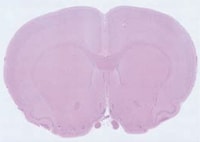

透射照明一般适用于两种样本:透明或半透明物体,或者需要在背光条件下进行测量的不透明物体。在透射照明模式下,光线从物体背后射出,穿透物体,最后被人眼或相机接收。透射照明主要用于通过载玻片或其他标本夹进行细胞或组织成像的生物应用场合。透射照明还适用于背光条件下的物体测量,可显示物体的细致轮廓,从而实现精确测量。

(200×,由120幅图像组成)